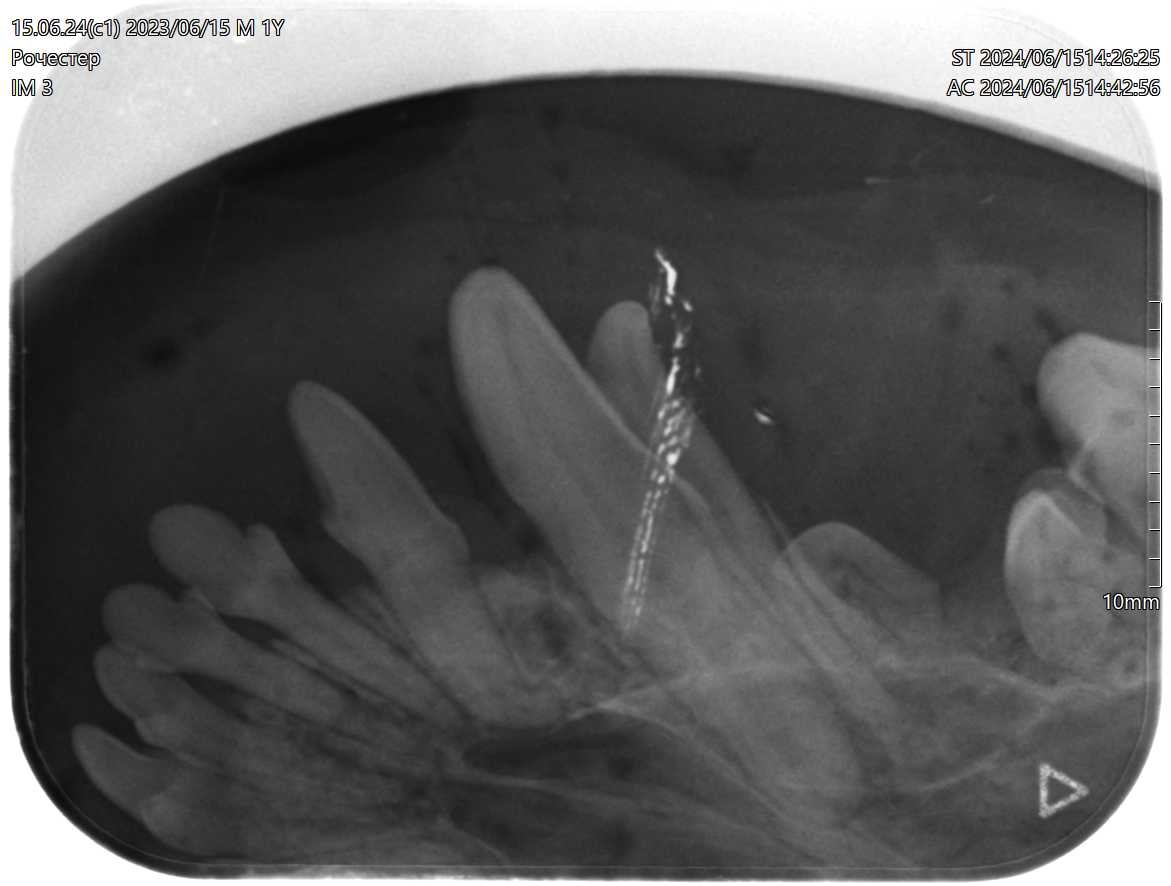

Персистирующие временные зубы у годовалого йоркширского терьера